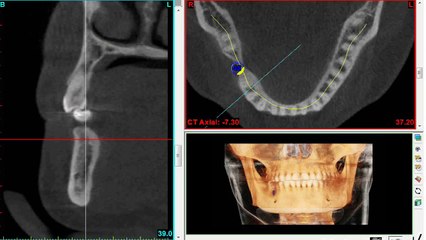

is Dr. Brazis' video blog about many aspects of dentistry. In this video, Dr. Brazis and Dr. Phelps discuss bone augmentation and sinus lift procedures as related to placement of dental implants. Distributed by Tubemogul.